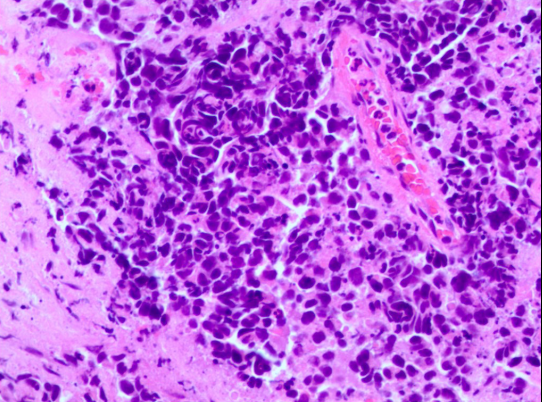

气管镜检查(2023-2-6):组织学形态结合免疫组化结果肿瘤细胞CK (核旁点灶状+)、TTF-1(+)、Syn(+)、CD56(+)、Ki-67(约90%+)、CD3( -)、CD20(-) 提示转化为小细胞癌。

图3. 气管镜活检病理结果提示小细胞癌转化